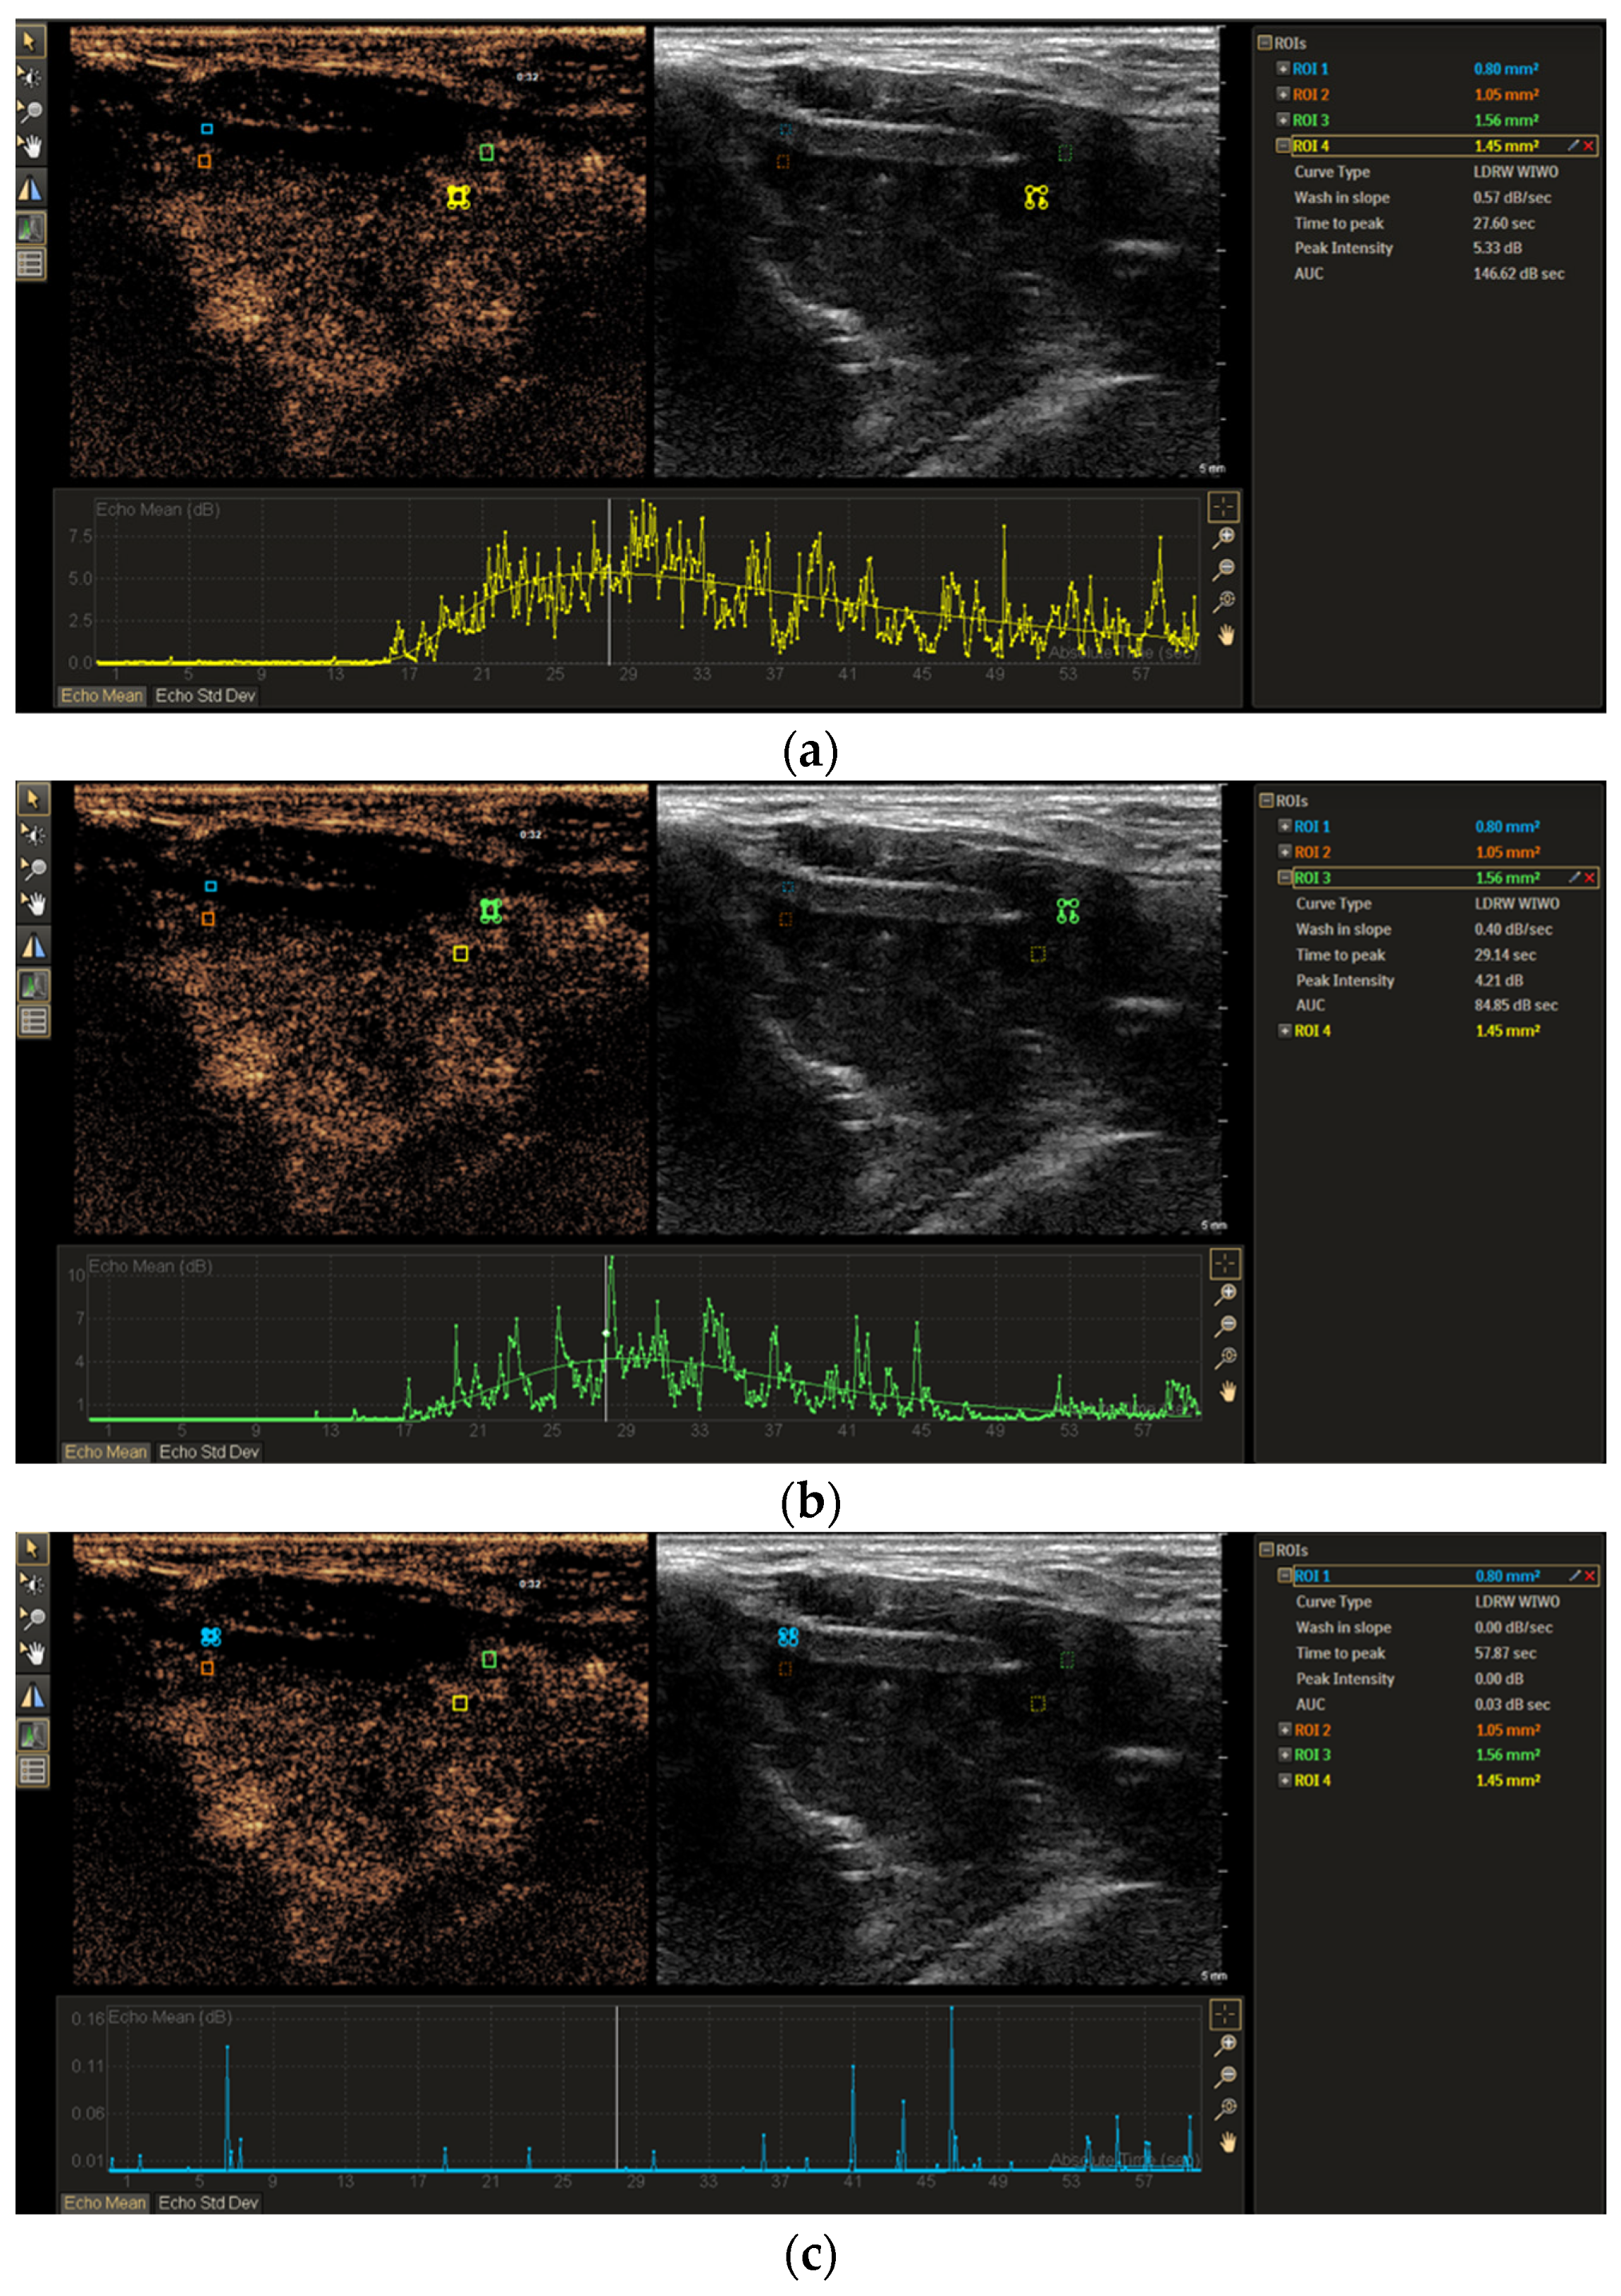

3.1. CEUS Imaging Features of Non-Ossified Thyroid Cartilage

3.2. TIC Analysis of Non-Ossified Thyroid Cartilage and Tumor Tissue